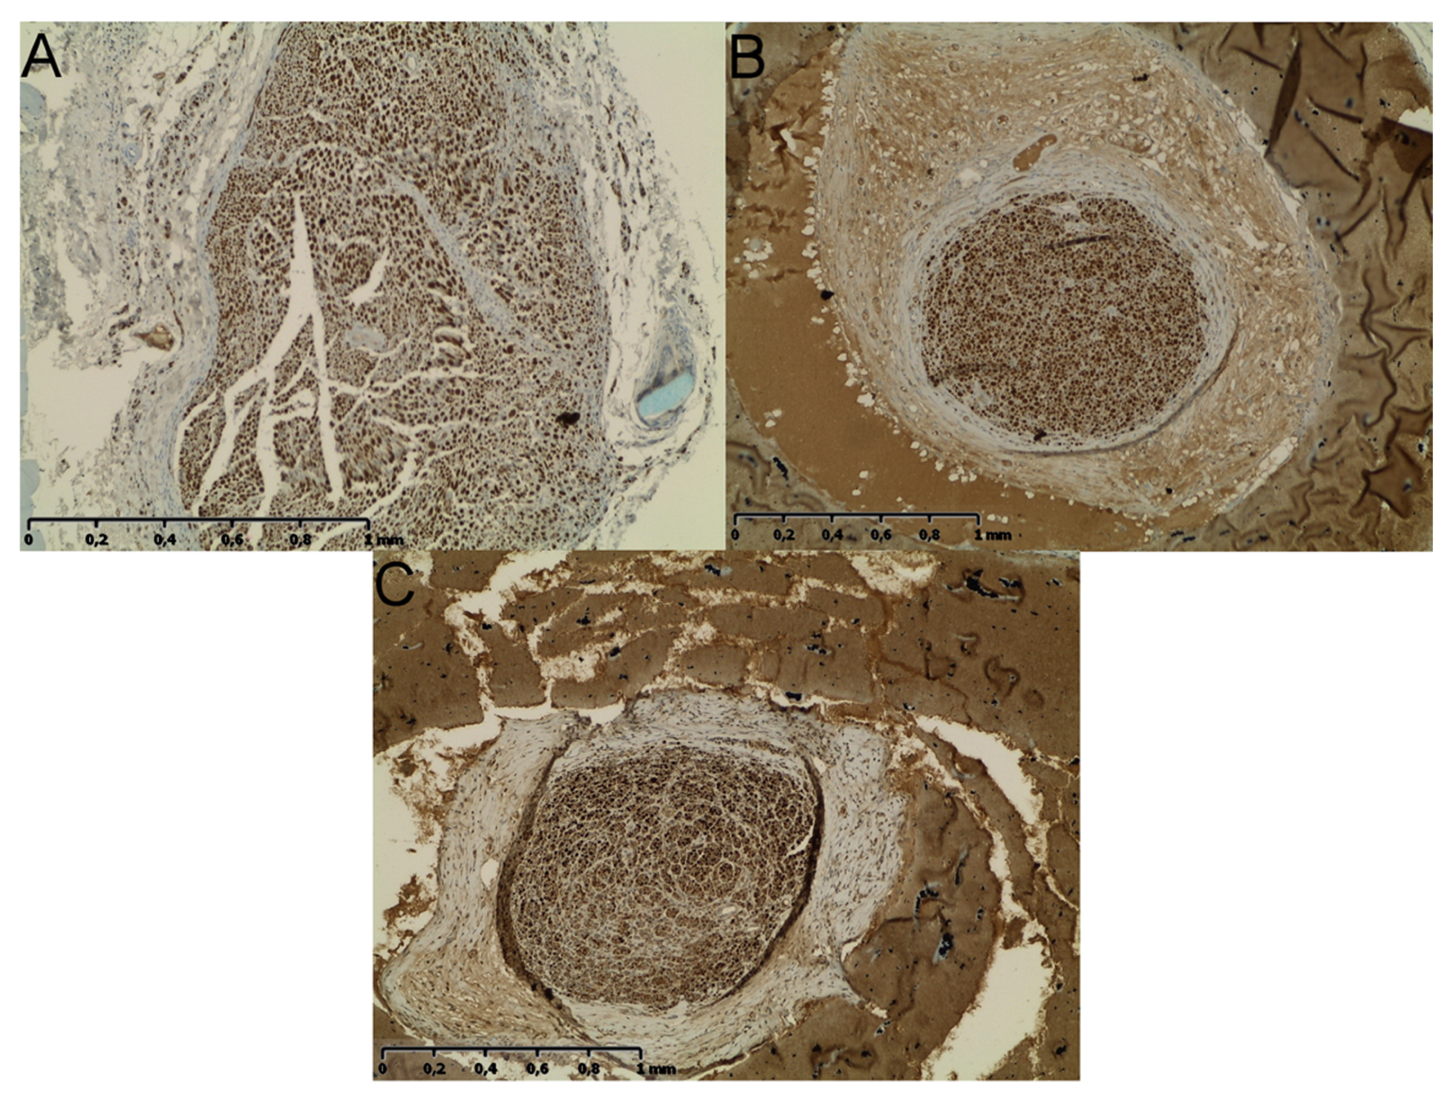

2.5. Neural Tissue